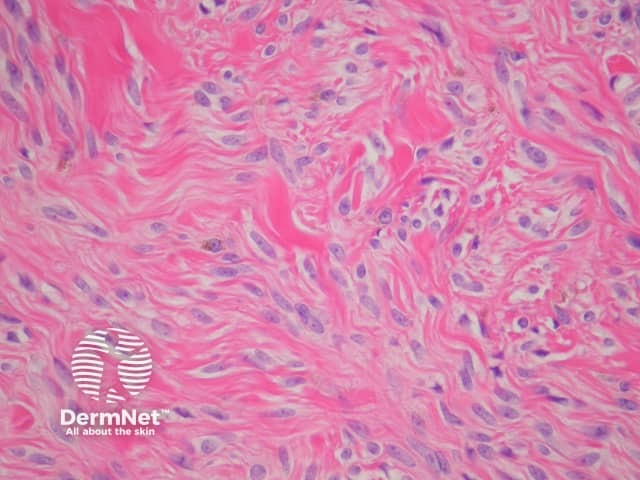

Histopathologically, blue naevi have a collection of dendritic melanocytes in the dermis (figure 2). Pure common blue naevi should not involve the epidermis. The connective tissue surrounding the melanocytes is usually sclerotic, sometimes profoundly so, when it is described as a sclerotic blue naevus. Aggregation of melanocytes about appendages and neurovascular bundles is common. Melanophages are usually also present in large numbers, which partially explains the blue clinical presentation.

Uncommonly, the dendritic melanocytes do not produce melanin (amelanotic blue naevus). These cases can cause diagnostic confusion due to their morphologic similarity to dermatofibroma or an extremely difficult desmoplastic melanoma (figure 3). Remarkably, cutaneous metastases of conventional melanoma can appear morphologically identical to blue naevi.

Figure 2

Figure 3